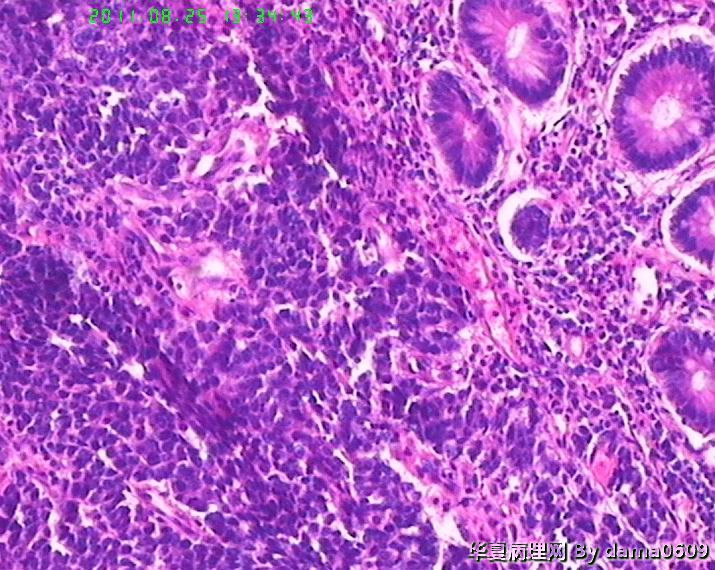

患者男性,39岁。以回盲部肿物行肠镜检查、活检。镜下四块组织内有两块见呈巢状的小细胞(如图

),另两块为粘膜慢性炎表现及坏死组织。学生不知如何分类:未分化癌?类癌?小细胞癌?请老师指教。谢谢!

细胞核较小、深染、一致,核分裂象少见,支持典型类癌。

神经内分泌肿瘤 淋巴瘤 低分化腺癌。。。

神经内分泌肿瘤

又仔细看了一下片子,有核仁,见到核分裂,是否可以定“未分化腺癌”呢?

楼主是想说“未分化癌”?片子切的比较厚,考虑神经内分泌肿瘤,低分化腺癌待排。

神经内分泌肿瘤?低分化腺癌?标一下神经内分泌标记

高级别癌,活检标本,可做IHC先排除高级别神经内分泌肿瘤。

如果神经内分泌阴性,明确分型等手术根治标本。